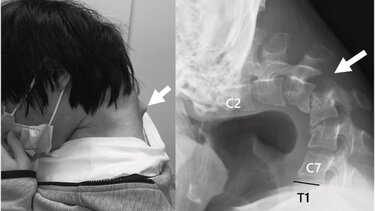

Αποτέλεσμα αυτής της στάσης ήταν να αναπτυχθεί ένα εξόγκωμα στον αυχένα, ενώ ο ίδιος έχασε πλήρως την ικανότητα να σηκώνει το κεφάλι του. Η κάμψη ήταν τόσο προχωρημένη, που το πηγούνι του ακουμπούσε μόνιμα στο στήθος.

Το 2023, ο νεαρός άρχισε να υποφέρει από αφόρητο πόνο στον αυχένα και δυσκολία στην κατάποση, η οποία προκάλεσε ταχεία απώλεια βάρους. Οι ιατρικές εξετάσεις αποκάλυψαν έντονη παραμόρφωση των αυχενικών σπονδύλων, καθώς και βλάβη στην ανώτερη σπονδυλική στήλη – συνέπειες της μακροχρόνιας καταπόνησης και υπερέκτασης των μυών του αυχένα.